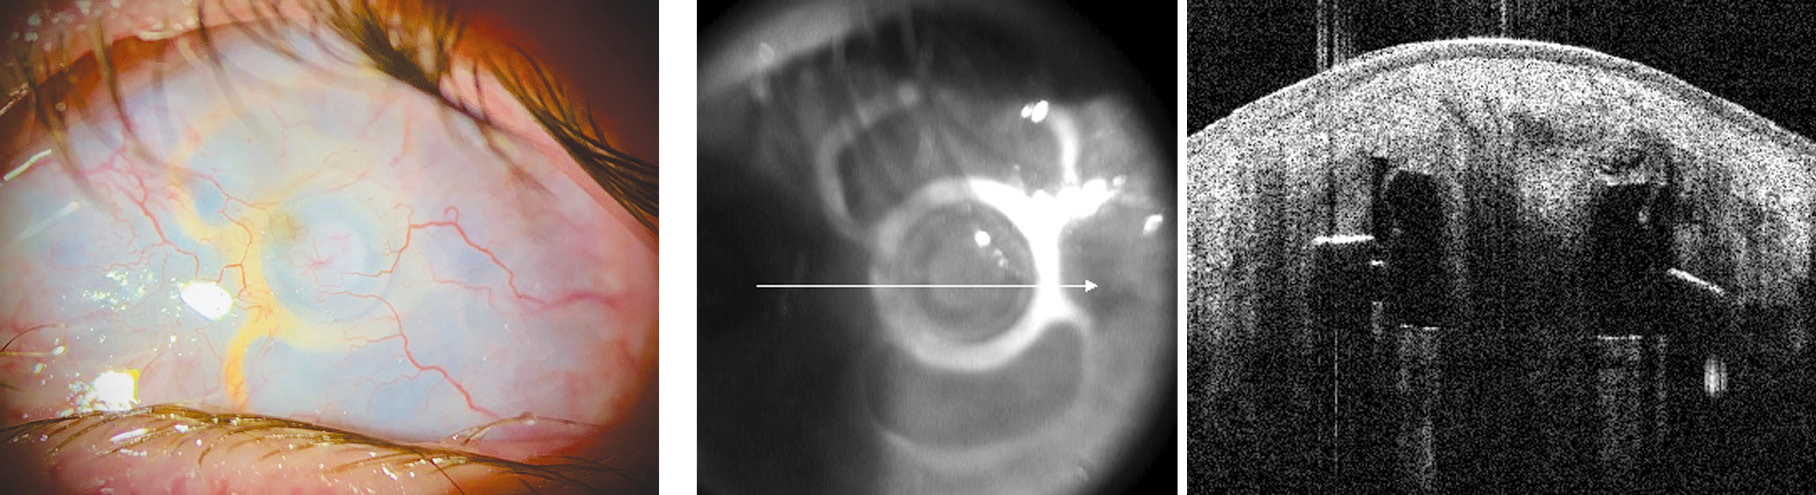

The postoperative period was uneventful, with no evidence of protrusion of the keratoprosthesis supporting element (outside or into the anterior chamber). Six months later, in May 2023, the second stage of the keratoprosthetics was performed: implantation of a 58 D optical cylinder with a protrusion height of 1.5 mm (Fig. 4).

Fig. 4. The results of the second stage of the Fyodorov–Zuev keratoprosthesis implantation on the left eye (positioning of the optical cylinder into the support keratoprosthesis element)

Рис. 4. Результаты второго этапа кератопротезирования (установка оптического цилиндра) на левом глазу

The postoperative period was uneventful, with no signs of infection or external filtration, and the patient reported an improvement in uncorrected visual acuity to 0.02. Sonography showed a flat serous detachment of the choroid, which resolved with instillations of dexamethasone 0.1% (4 times daily) for 1 week. A small blood clot behind the optical cylinder was lysed within 2 weeks. Uncorrected visual acuity improved to 0.1. In the postoperative period, in addition to dexamethasone, the patient received instillations of levofloxacin 0.5% (4 times daily for 10 days) and continued therapy with lubricants containing hyaluronate 0.3% (8 times a day).

At 1 month postoperatively, uncorrected visual acuity was 0.2 in the left eye, and the supporting element and optical cylinder of the keratoprosthesis were correctly positioned with no evidence of protrusion.

Six months after surgery, the uncorrected visual acuity of the left eye remained the same (0.2), and the position of the supporting element and the optical cylinder of the keratoprosthesis did not change (Fig. 6).

Fig. 6. Biomicroscopic appearance six months after the second stage of keratoprosthetics

Рис. 6. Биомикроскопическая картина через полгода после второго этапа кератопротезирования